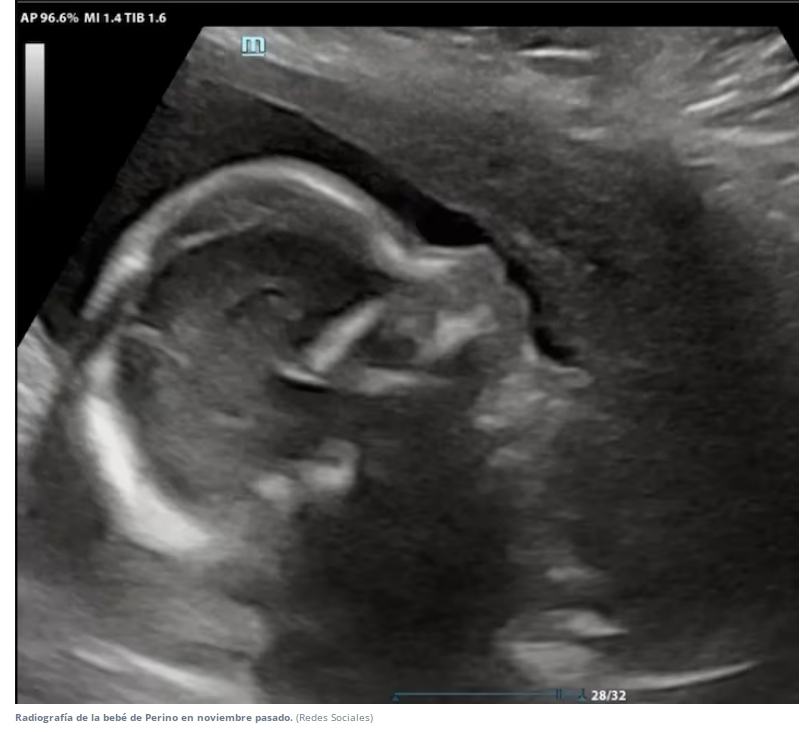

La pareja acordó que la gestante iba a ser Natalí. Los procedimientos los realizó en una clínica de la localidad bonaerense de San Isidro. Primero había realizado técnicas y tratamientos de baja complejidad, y luego pasó a las de alta (cuando la unión entre el óvulo y el espermatozoide se produce fuera del cuerpo, o cuando se vitrifican tejidos vivos). Así, tras un largo proceso de intervenciones médicas, la mujer consiguió quedar embarazada en julio pasado.

Pasaron los meses y su embarazo transcurría de forma saludable. Sin embargo, la relación con quien había imaginado formar una familia se rompió. A medio camino, su expareja se arrepintió del proyecto e intentó desvincularse, lo que generó varios inconvenientes legales, ya que impedía el trámite de registro y adquisición de la partida de nacimiento del bebé.

En medio del doloroso duelo por la ruptura de su relación de pareja, Perino ratificó su deseo de ser madre y decidió conformar un hogar monoparental. Su bebé nació sin complicaciones el 6 de marzo pasado. Natalí la abrazó, le dio el pecho y le puso un nombre. Sin embargo, en el plano legal, la recién nacida no pudo ser identificada en el Registro civil porteño.